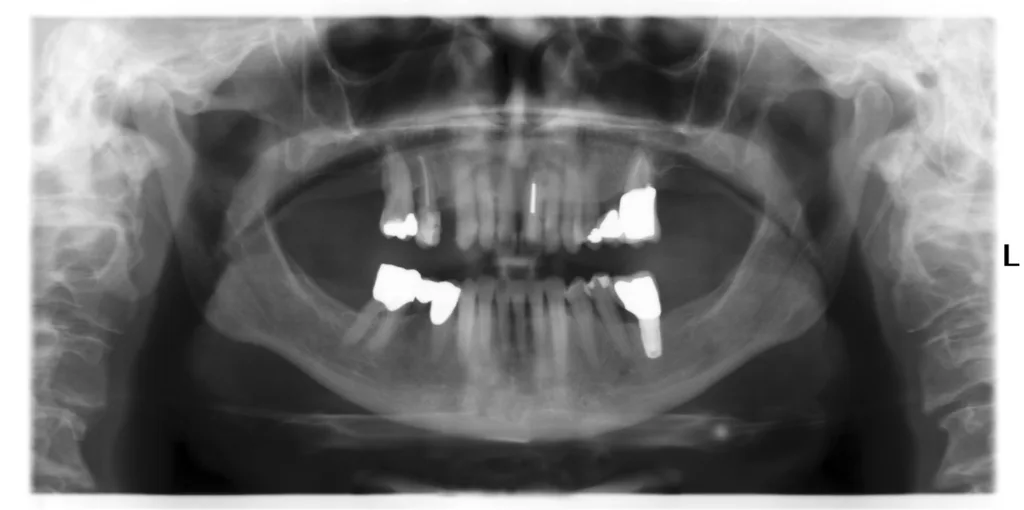

Digitalisierung bedeutet Information und Sicherheit. Die Erstellung eines DVTs in der frühen Implantatplanung hat drei Kernvorteile:

- Anatomische Information: Mehrinformationen sind die Nähe zum N. alveolaris, die Ausdehnung der Kieferhöhle und ihrer Septen, der Verlauf (insbesondere transversal) und die Mineralisation des Implantatknochens (nach Zahnextraktion) sowie die Positionierung des/r Implantate/s in Relation zu Nachbarzähnen (Abb. 9 und 10). Durch Schrägmessungen resultieren auch im DVT-Messfehler von bis zu 1 mm [5,6].

- Präzision: Die 3D-Beurteilung des Implantatgebietes bedeutet einen erhöhten Zeitaufwand in der Planung, die im Regelfall auch zu einer präziseren, schonenden und risikoärmeren OP-Planung und Implantatinsertion führt. Auch bei langjähriger klinischer Erfahrung sollte dieser Vorteil genutzt werden.

Die Abrechnung des DVTs erfolgt durch die in der GOÄ für Zahnärzte/-innen geöffneten GOÄ-Pos. 5370 und 5377. Besitzt man kein eigenes DVT, sind chirurgisch tätige Kollegen/-innen (Überweisende) oder speziell ausgerüstete Radiologiepraxen Ansprechpartner/-innen. Achtung: DVT-Aufnahme (Region, Ausschnitt, Viewer etc.) immer individuell anweisen. Der Mehraufwand der 3D-Analyse und Auswertung wird mittels Analogposition (GOZ 9000a) berechnet.